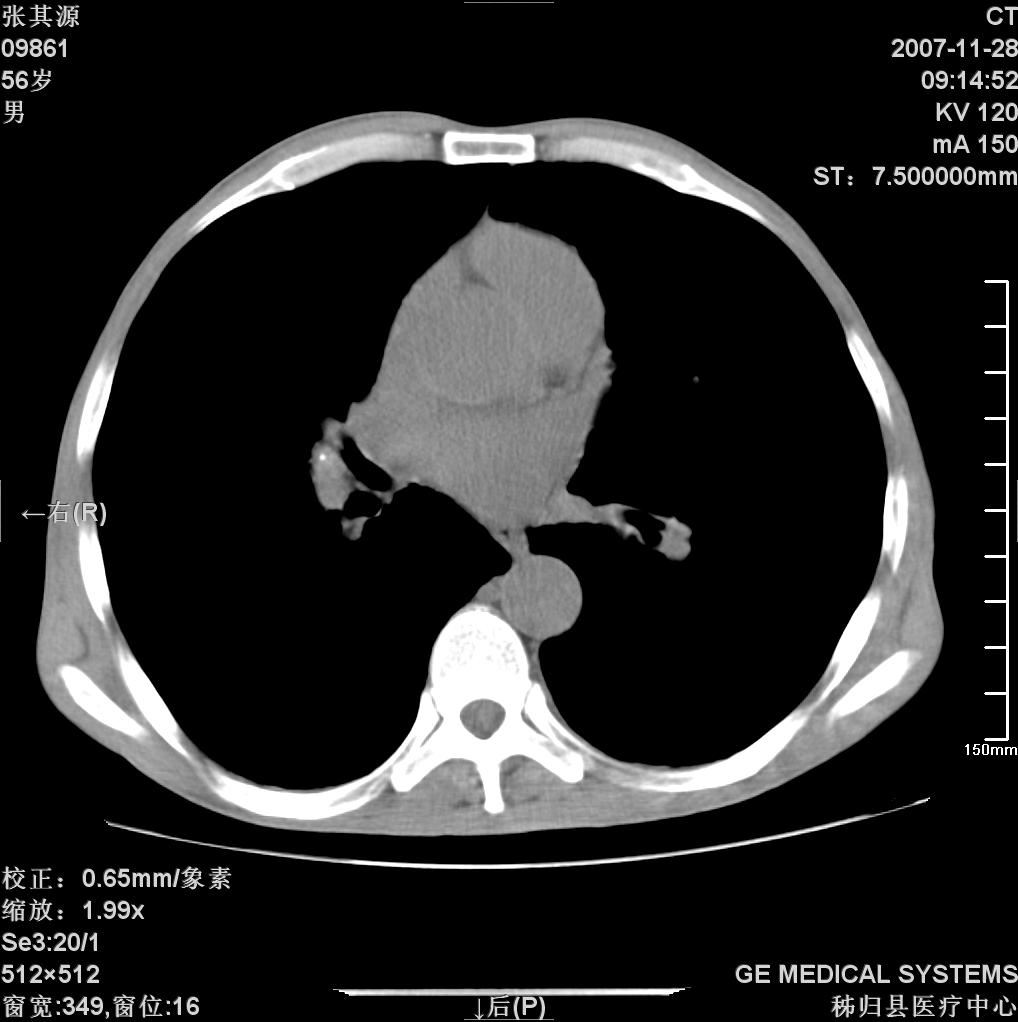

患者因阻塞性黄疸入院,发病前10天持续中等程度发烧.术前检查发现两肺弥漫性病变,请各位大虾会诊,除了考虑急性血源性肺结核外,还有其他什么疾病可能.

补充一下,该患者没有与尘肺相关职业史。请大家帮忙会诊一下,外科医生打算为其做胆总管肿瘤做手术的,现在在等我们的结果。谢谢各位了。

双肺多发粟粒样病灶,右肺胸膜下结节样病灶,气管前腔静脉后及隆突下均见肿大淋巴结,结合胆道肿瘤病史首先考虑转移。另外心影密度略低,时间格显示,是否有贫血?查明白再手术吧!